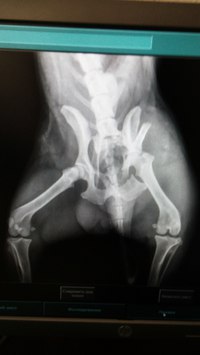

Диагноз-перелом таза со смещением-перелом подвзошной кости слева. Рекомендована операция. Стоимость операции 15 000руб.